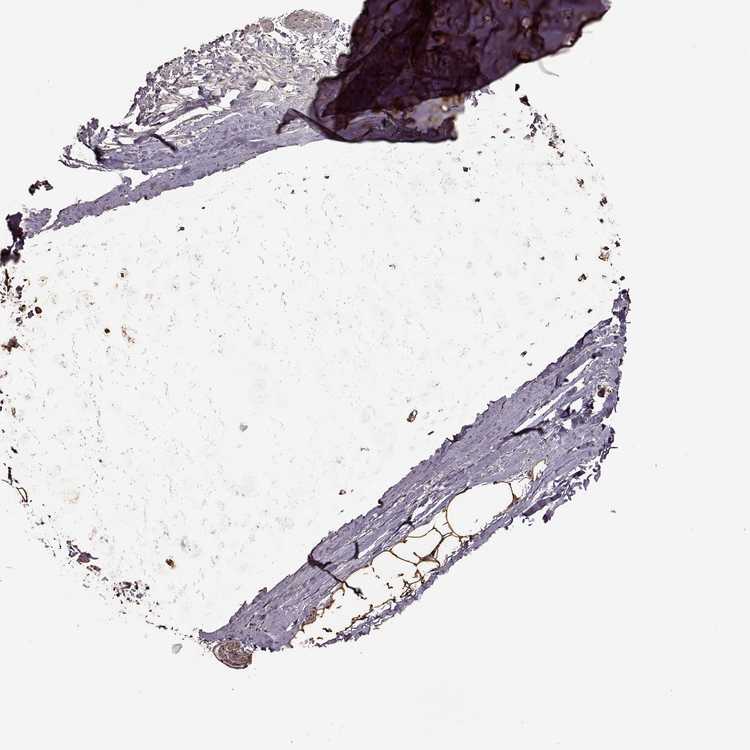

SOFT TISSUE 2 - Antibody stainingi

Antibody staining in the annotated cell types in the current human tissue is reported as not detected, low, medium, or high, based on conventional immunohistochemistry profiling in selected tissues. This score is based on the combination of the staining intensity and fraction of stained cells.

Each image is clickable and will lead to virtual microscopy that enables deeper exploration of all samples and also displays staining intensity scores, fraction scores and subcellular localization as well as patient and tissue information for each sample.

Antibody HPA072204

Fibroblasts Low

Peripheral nerve High